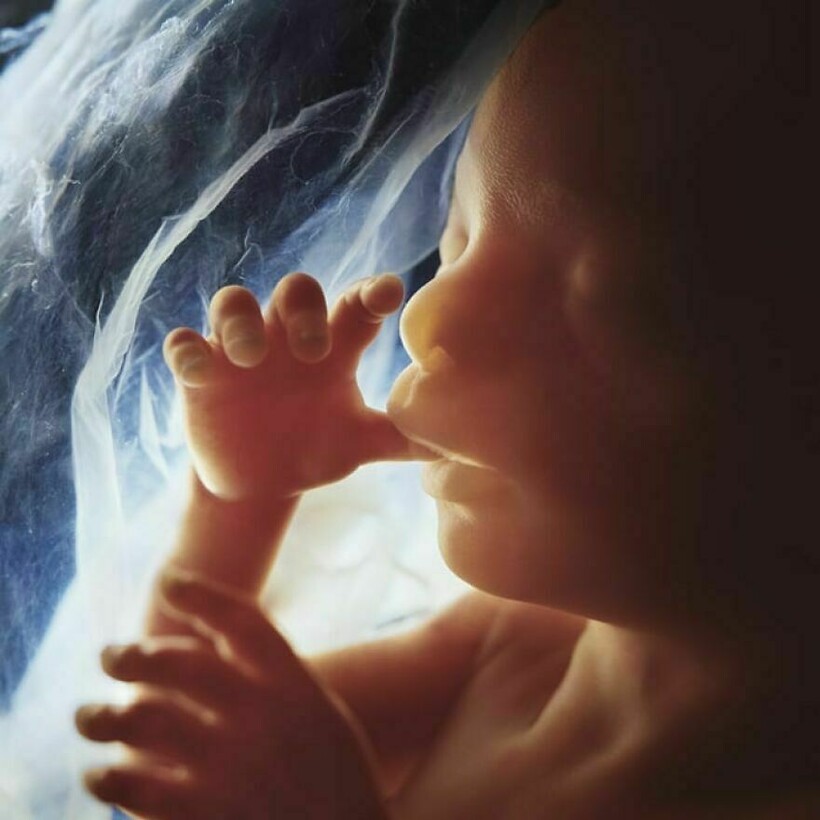

Леннарт Нильссон стал настоящей легендой фотографии, ведь он сделал то, чего не удавалось никому: показал миру, как развивается ребенок в утробе матери. Его проект «Ребенок родился» был создан в 1960-х годах, и он представляет собой детальные снимки эмбрионов на разных стадиях развития. Фотографии стали сенсационными, впервые они появились в журнале LIFE, и одна из них украсила обложку. На протяжении многих лет эти снимки публиковали в разных журналах.

Снимки стали сенсацией, их много раз перепечатывали, они и сегодня вызывают отклик у зрителей

Его фото позволили заглянуть в чудо рождения, они стали источником знаний и вдохновения

Нильссон помог людям лучше понять себя и свое тело

Сделать невидимое видимым и донести науку до общественности

Почти все эти снимки сделаны в 1965 году, однако Нильссон фотографировал до конца своей жизни, и запечатлел не только развитие эмбриона, но и само зарождение жизни: вот тут мы собрали другие его фотографии.